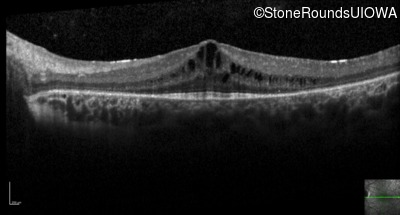

Visit at age: 21 years

Optical Coherence Tomography - Right - 20/25 -2

Exemplar / OCT Stack